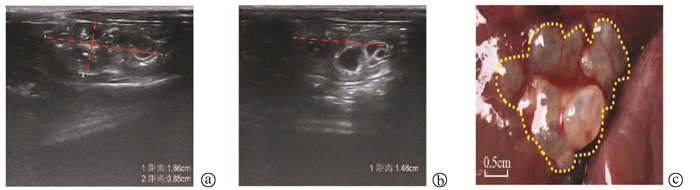

Chinese expert consensus on the endoscopic diagnosis and treatment of biliary fistula (2020, Beijing)

Abstract(1246) HTML (675) PDF (1978KB)(242)

Chinese expert consensus on the endoscopic diagnosis and treatment of pancreatic fistula (2020, Beijing)

Abstract: